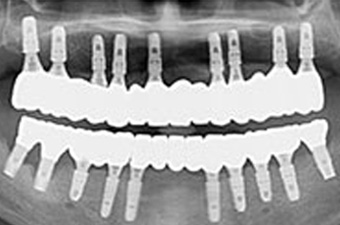

보험 임플란트 치료과정

01

CT촬영 및 구강스캔으로

잇몸뼈분석하여 치아의 상태를 체크

image.png

02

임플란트 식립은 필요 개수만큼 식립 후 여러개의 치아가 하나로 연결된 브릿지 형태 보철물을 필요에 따라 맞춤 제작

03

상악과 마찬가지로 임플란트 식립 후 브릿지 형태로 맞춤 제작해 사용

04

일상생활의 불편함을 줄이기 위해 당일 임시치아를 결합하여 일상생활이 가능